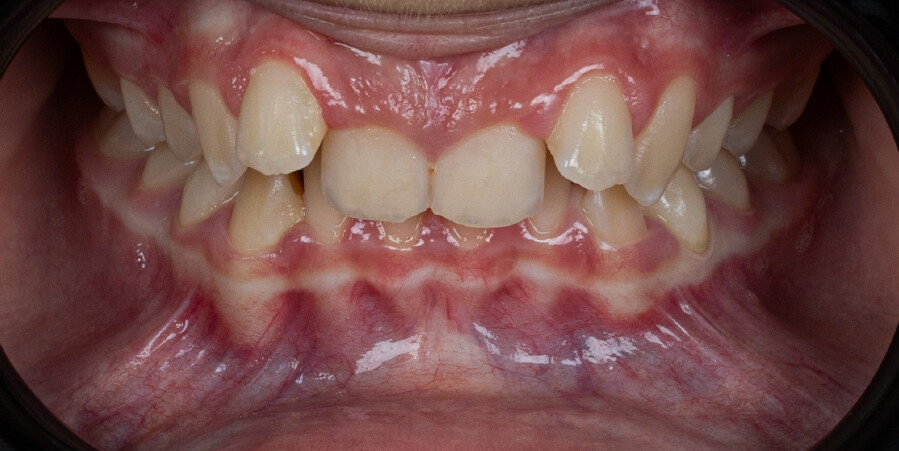

Um paciente do sexo masculino, com 13 anos de idade, apresentou-se com uma mordida profunda, caracterizada pela cobertura quase completa dos incisivos mandibulares. A avaliação clínica revelou apinhamento em ambas as arcadas, rotações dentárias e proclinação dos incisivos laterais superiores, contribuindo para as preocupações estéticas do paciente. O perfil facial era retrusivo, consistente com retrognatismo mandibular, e não foram detectadas anomalias periodontais significativas.

DIAGNÓSTICO:

O paciente apresentava uma relação esquelética de Classe II com molares e caninos bilaterais em Classe II e um padrão dentário de Classe II divisão 2. A mordida profunda estava associada a um apinhamento anteroinferior e a uma curva de Spee acentuada. A análise facial revelou boa simetria, um terço facial inferior ligeiramente aumentado e um perfil convexo caracterizado por retrusão mandibular e do mento. A competência labial estava ligeiramente reduzida, com diminuição do ângulo nasolabial e leve tensão do músculo mentoniano, fatores que comprometiam a harmonia facial global.